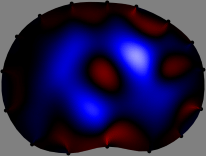

for [23]. This shows that the column vector is like an EEG (electroencephalography) data induced by dipole sources with directions at locations . Given that two dipole sources at distant locations produce mutually independent data, the correlation between and decreases with the distance between and . Fig. 2 shows a few images of the correlation as a function of for four different positions . The correlation decreases rapidly as the distance increases. In the green regions where the correlation is almost zero, is nearly orthogonal to .

Fig. 2 shows that if and are far from each other, the corresponding columns of the sensitivity matrix are nearly orthogonal. This somewhat orthogonal structure of the sensitivity matrix motivates an algebraic formula that directly computes the local ensemble average of conductivity changes at each point using the inner product between changes in the data and a scaled sensitivity vector at that point: